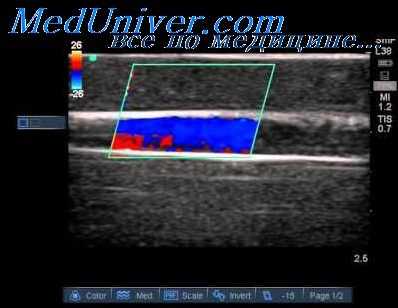

Рис. 2. Увеличение псевдопульсации и интенсивности потока в прямом синусе. Транскраниальная допплерография (субокципитальное окно)

Рис. 3. Увеличение кровотока в прямом синусе и вене Розенталя. Транскраниальная допплерография (субокципитальное и темпоральные окна)